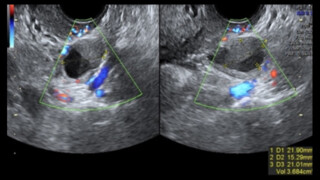

Quelle médecine pour les français ? Endométriose : Le rôle central de l’imagerie

Le mois de mars est depuis plusieurs années l’occasion de sensibiliser le grand public à une maladie peu ou mal connue, l’endométriose. Touchant plus d’1 femme sur 10 en âge de procréer, elle est ... lire la suite >>